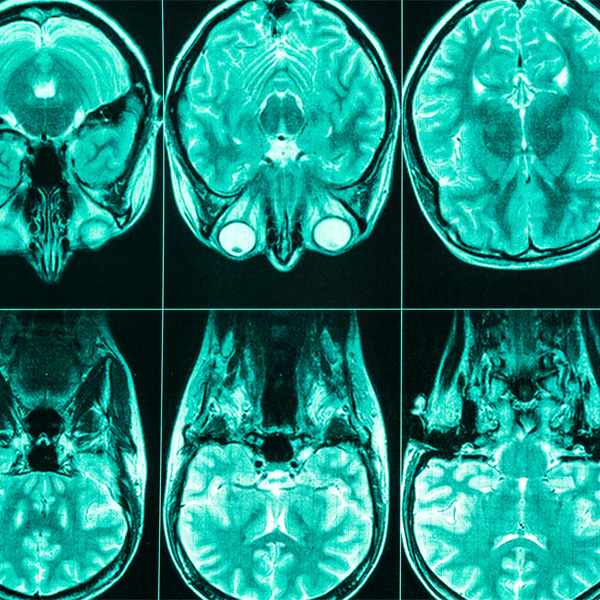

An MRI scan of a head